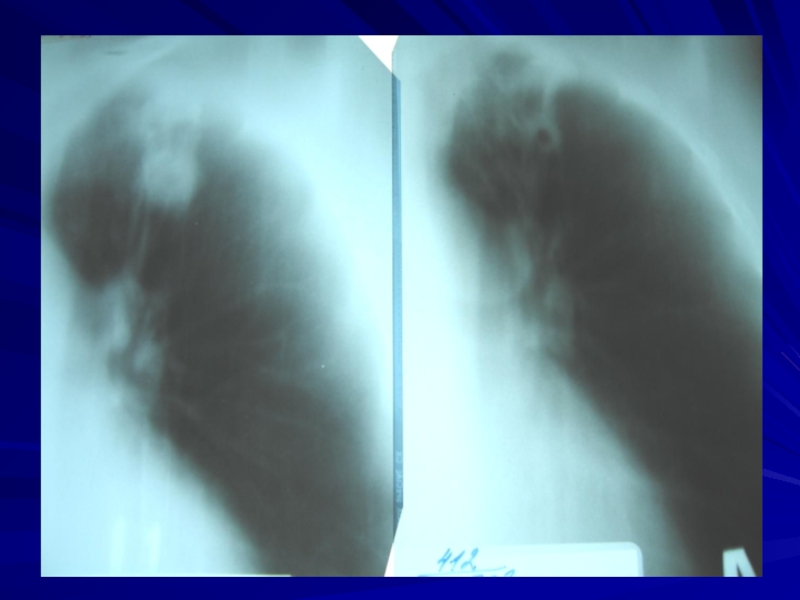

Слайд 17Туберкулез внутригрудных лимфатических узлов

Слайд 19Плеврит

Слайд 20Очаговый туберкулёз